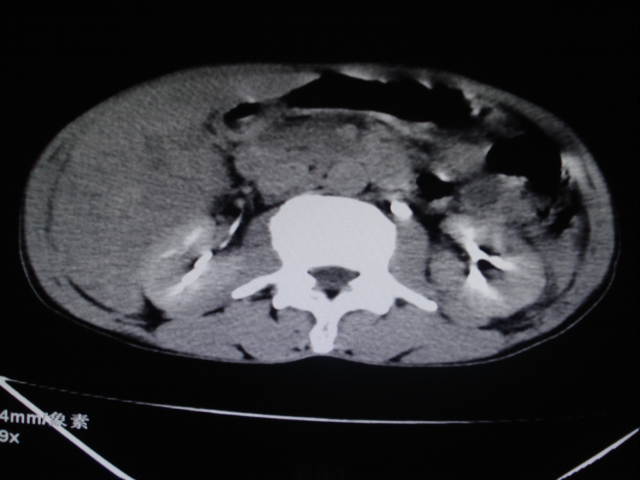

男性,62岁。肝右叶占位,平扫及增强如下,延迟期为15分钟扫描。